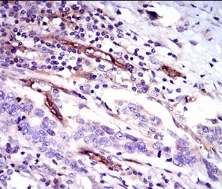

CD59 Mouse Monoclonal antibody[8D2B8]

This gene encodes a cell surface glycoprotein that regulates complement-mediated cell lysis, and it is involved in lymphocyte signal transduction. This protein is a potent inhibitor of the complement membrane attack complex, whereby it binds complement C8 and/or C9 during the assembly of this complex, thereby inhibiting the incorporation of multiple copies of C9 into the complex, which is necessary for osmolytic pore formation. This protein also plays a role in signal transduction pathways in the activation of T cells. Mutations in this gene cause CD59 deficiency, a disease resulting in hemolytic anemia and thrombosis, and which causes cerebral infarction. Multiple alternatively spliced transcript variants, which encode the same protein, have been identified for this gene.

IHC    1/200 - 1/1000